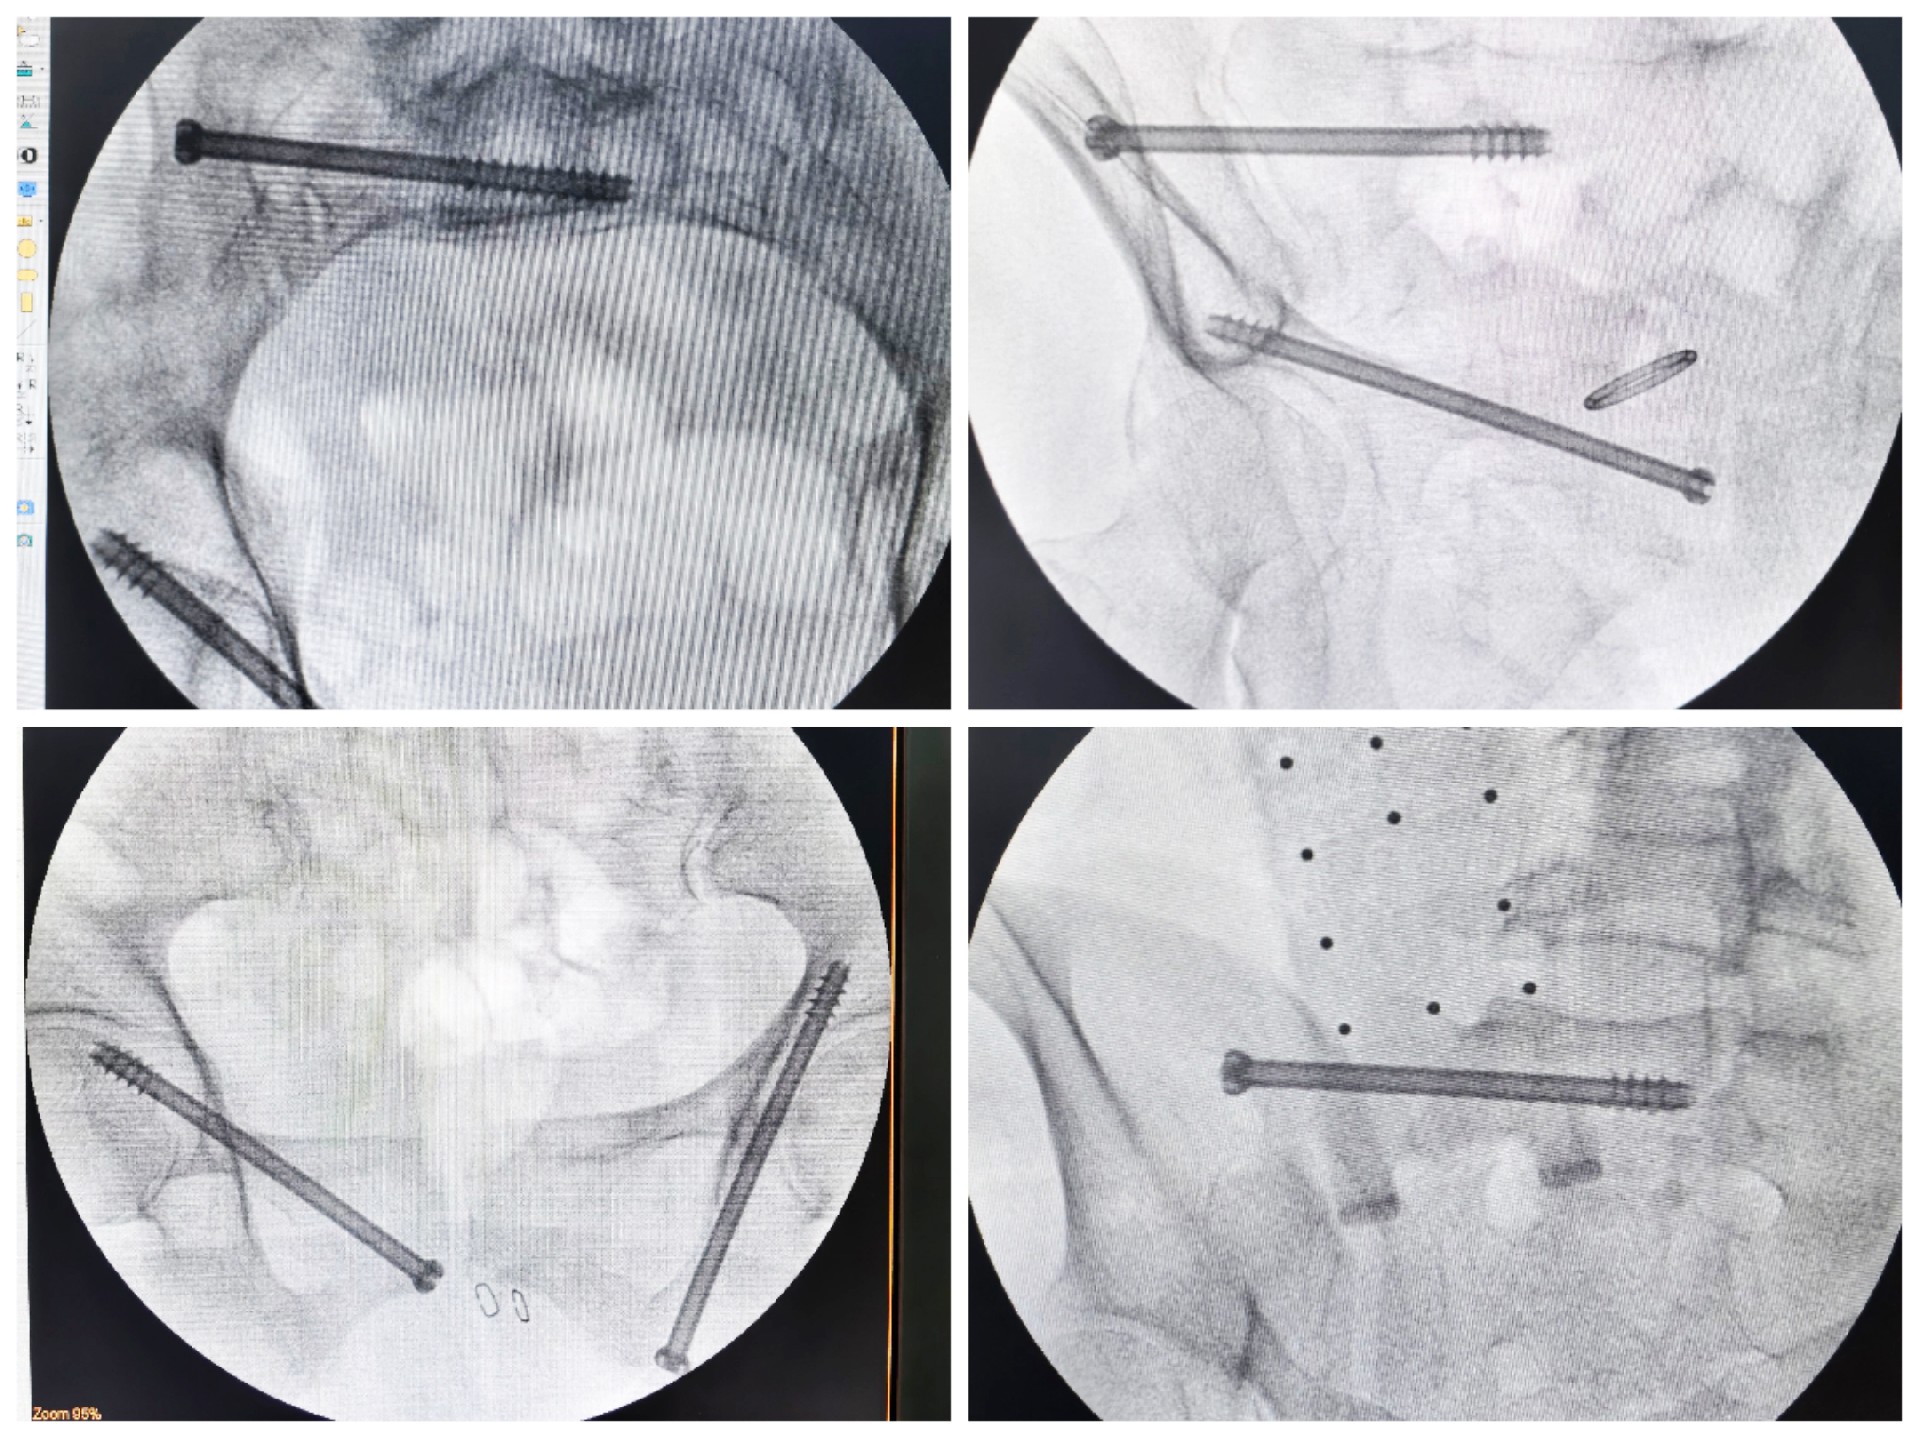

傳統(tǒng)的骨盆骨折微創(chuàng)手術(shù)中,骶髂螺釘?shù)嚷葆斨萌氲碾y點(diǎn)在于骨盆部位解剖十分復(fù)雜,螺釘置入如有偏差極易損傷重要神經(jīng)及血管,手術(shù)不僅依靠手術(shù)醫(yī)師豐富的經(jīng)驗(yàn),還需要術(shù)中反復(fù)的C型臂透視及調(diào)整,對(duì)患者及醫(yī)生都有較大輻射。而利用HoloSight知見創(chuàng)傷骨科機(jī)器人進(jìn)行骨盆骨折微創(chuàng)手術(shù),通過(guò)高精度光學(xué)定位追蹤技術(shù)與混合現(xiàn)實(shí)技術(shù),使整個(gè)微創(chuàng)手術(shù)全程可視化,可以在電腦屏幕上實(shí)時(shí)顯示螺釘?shù)木珳?zhǔn)置入位置,降低手術(shù)風(fēng)險(xiǎn),提高手術(shù)效率及安全性。

術(shù)前,手術(shù)團(tuán)隊(duì)認(rèn)真分析討論病例,全面掌握骨盆骨折微創(chuàng)治療的關(guān)鍵技術(shù),提前設(shè)計(jì)手術(shù)方案并反復(fù)模擬演練手術(shù)過(guò)程。術(shù)中,利用HoloSight知見創(chuàng)傷骨科機(jī)器人規(guī)劃骨折復(fù)位方案及定位螺釘通道,實(shí)現(xiàn)精準(zhǔn)微創(chuàng)手術(shù)。手術(shù)通過(guò)不足1cm小切口完成,最大程度地減少了術(shù)中出血,術(shù)中幾乎都是一次性成功精準(zhǔn)微創(chuàng)地置入內(nèi)固定螺釘,減少了醫(yī)源性操作對(duì)骨折周圍骨質(zhì)的影響,實(shí)現(xiàn)骨折微創(chuàng)固定的同時(shí)盡可能提高骨折固定的穩(wěn)定性,為術(shù)后患者的快速康復(fù)創(chuàng)造了有利條件。